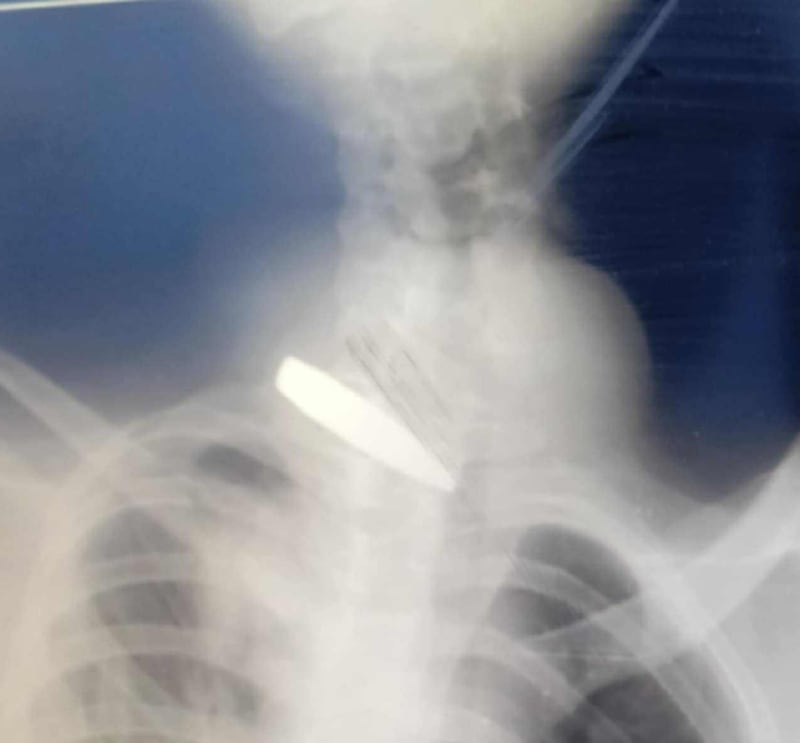

Liknande text är också mejlad till socialdepartementet. Bilden är en preoperativ röntgen från en av de drabbade i artikeln. Flera tidningar har nekat publicering av denna text.